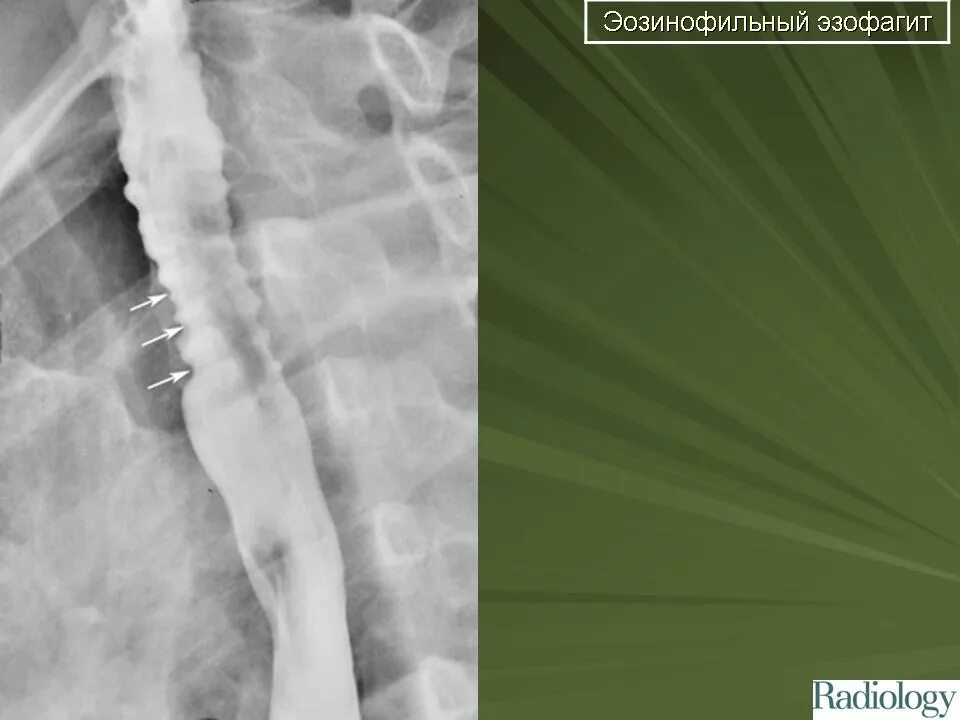

Кольцо шацкого в пищеводе что это